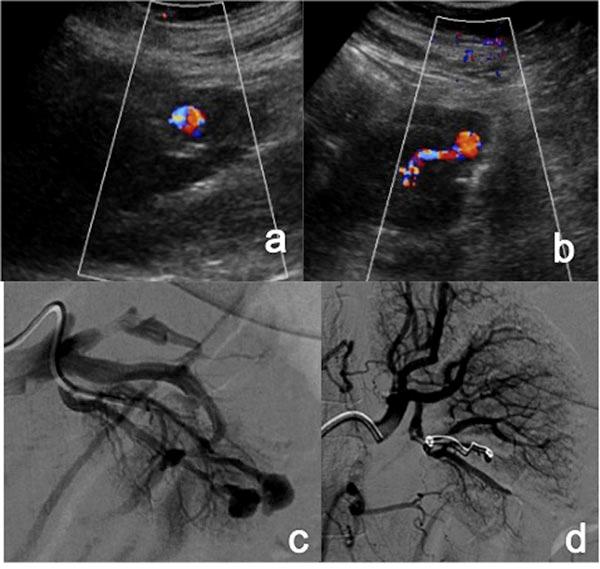

Acute vascular emergencies can arise from direct traumatic injury to the vessel or be spontaneous (non-traumatic).The vascular injuries can also be divided into two categories: arteial injury and venous injury.Most of them are life-treatening emergencies, sice they may cause an important ipovolemic shock or severe ischemia in their end organ and require prompt diagnosis and treatment.In the different clinical scenarios, the correct diagnostic approach to vascular injuries isn't firmly established and advantages of one imaging technique over the other are not obvious.Ultrasound (US) is an easy accessible, safe and non-invasive diagnostic modality but Computed Tomography (CT) with multiphasic imaging study is an accurate modality to evaluate the abdominal vascular injuries therefore can be considered the primary imaging modality in vascular emergencies.The aim of this review article is to illustrate the different imaging options for the diagnosis of abdominal vascular emergencies, including traumatic and non traumatic vessel injuries, focusing of US and CT modalities.

急性血管急症可由血管直接外伤引起,也可为自发性(非外伤性)。血管损伤也可分为两类:动脉损伤和静脉损伤。它们大多是危及生命的急症,因为它们可能导致重要的低血容量性休克或其终末器官的严重缺血,需要及时诊断和治疗。在不同的临床情况下,针对血管损伤的正确诊断方法尚未完全确立,一种成像技术相对于另一种成像技术的优势并不明显。超声(US)是一种易于获得、安全且无创的诊断方式,但多期成像研究的计算机断层扫描(CT)是评估腹部血管损伤的准确方式,因此可被视为血管急症的主要成像方式。本文综述的目的是阐述用于诊断腹部血管急症的不同成像选择,包括外伤性和非外伤性血管损伤,重点介绍超声和CT方式。